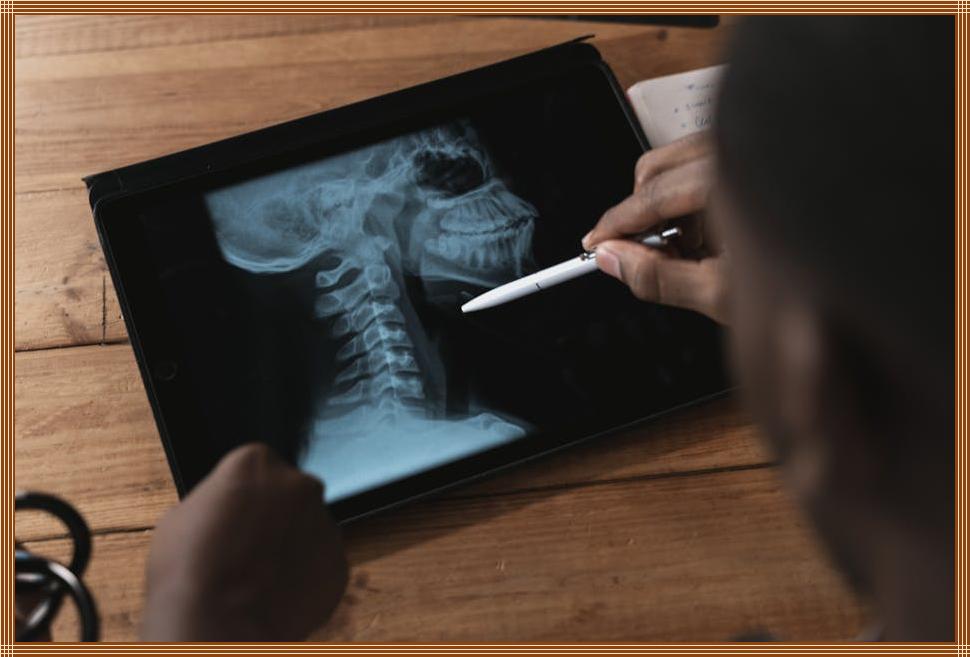

아이패드로 포토샵, 꿈은 현실로!

아이패드로 포토샵 작업을 시작하는 방법에 대한 완벽 가이드입니다. 휴대성과 강력한 성능을 갖춘 아이패드를 활용하여 사진 편집 실력을 향상시키고, 다양한 앱과 애플 펜슬을 통해 전문적인 결과물을 만들어보세요. 초보자를 위한 튜토리얼과 팁, 활용 분야까지, 아이패드 포토샵의 모든 것을 알아보세요.